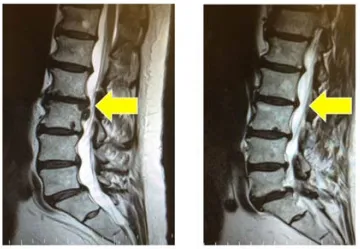

Spinal MRI

Non-Surgical Spinal Decompression is a non-invasive treatment for patients who suffer from neck and back problems. A decompression treatment slowly and gently lengthens or releases pressure in the spine through repetitive movements by a customized medical device. The table pulls and releases, creating a pressure change within the intervertebral disc, surrounding soft tissue, and joints. This pressure change allows the disc bulges or herniations and nutrients to be pulled back into the disc. Re-hydration of the disc and surrounding tissues creates a physiological change which assists the body’s natural healing process.